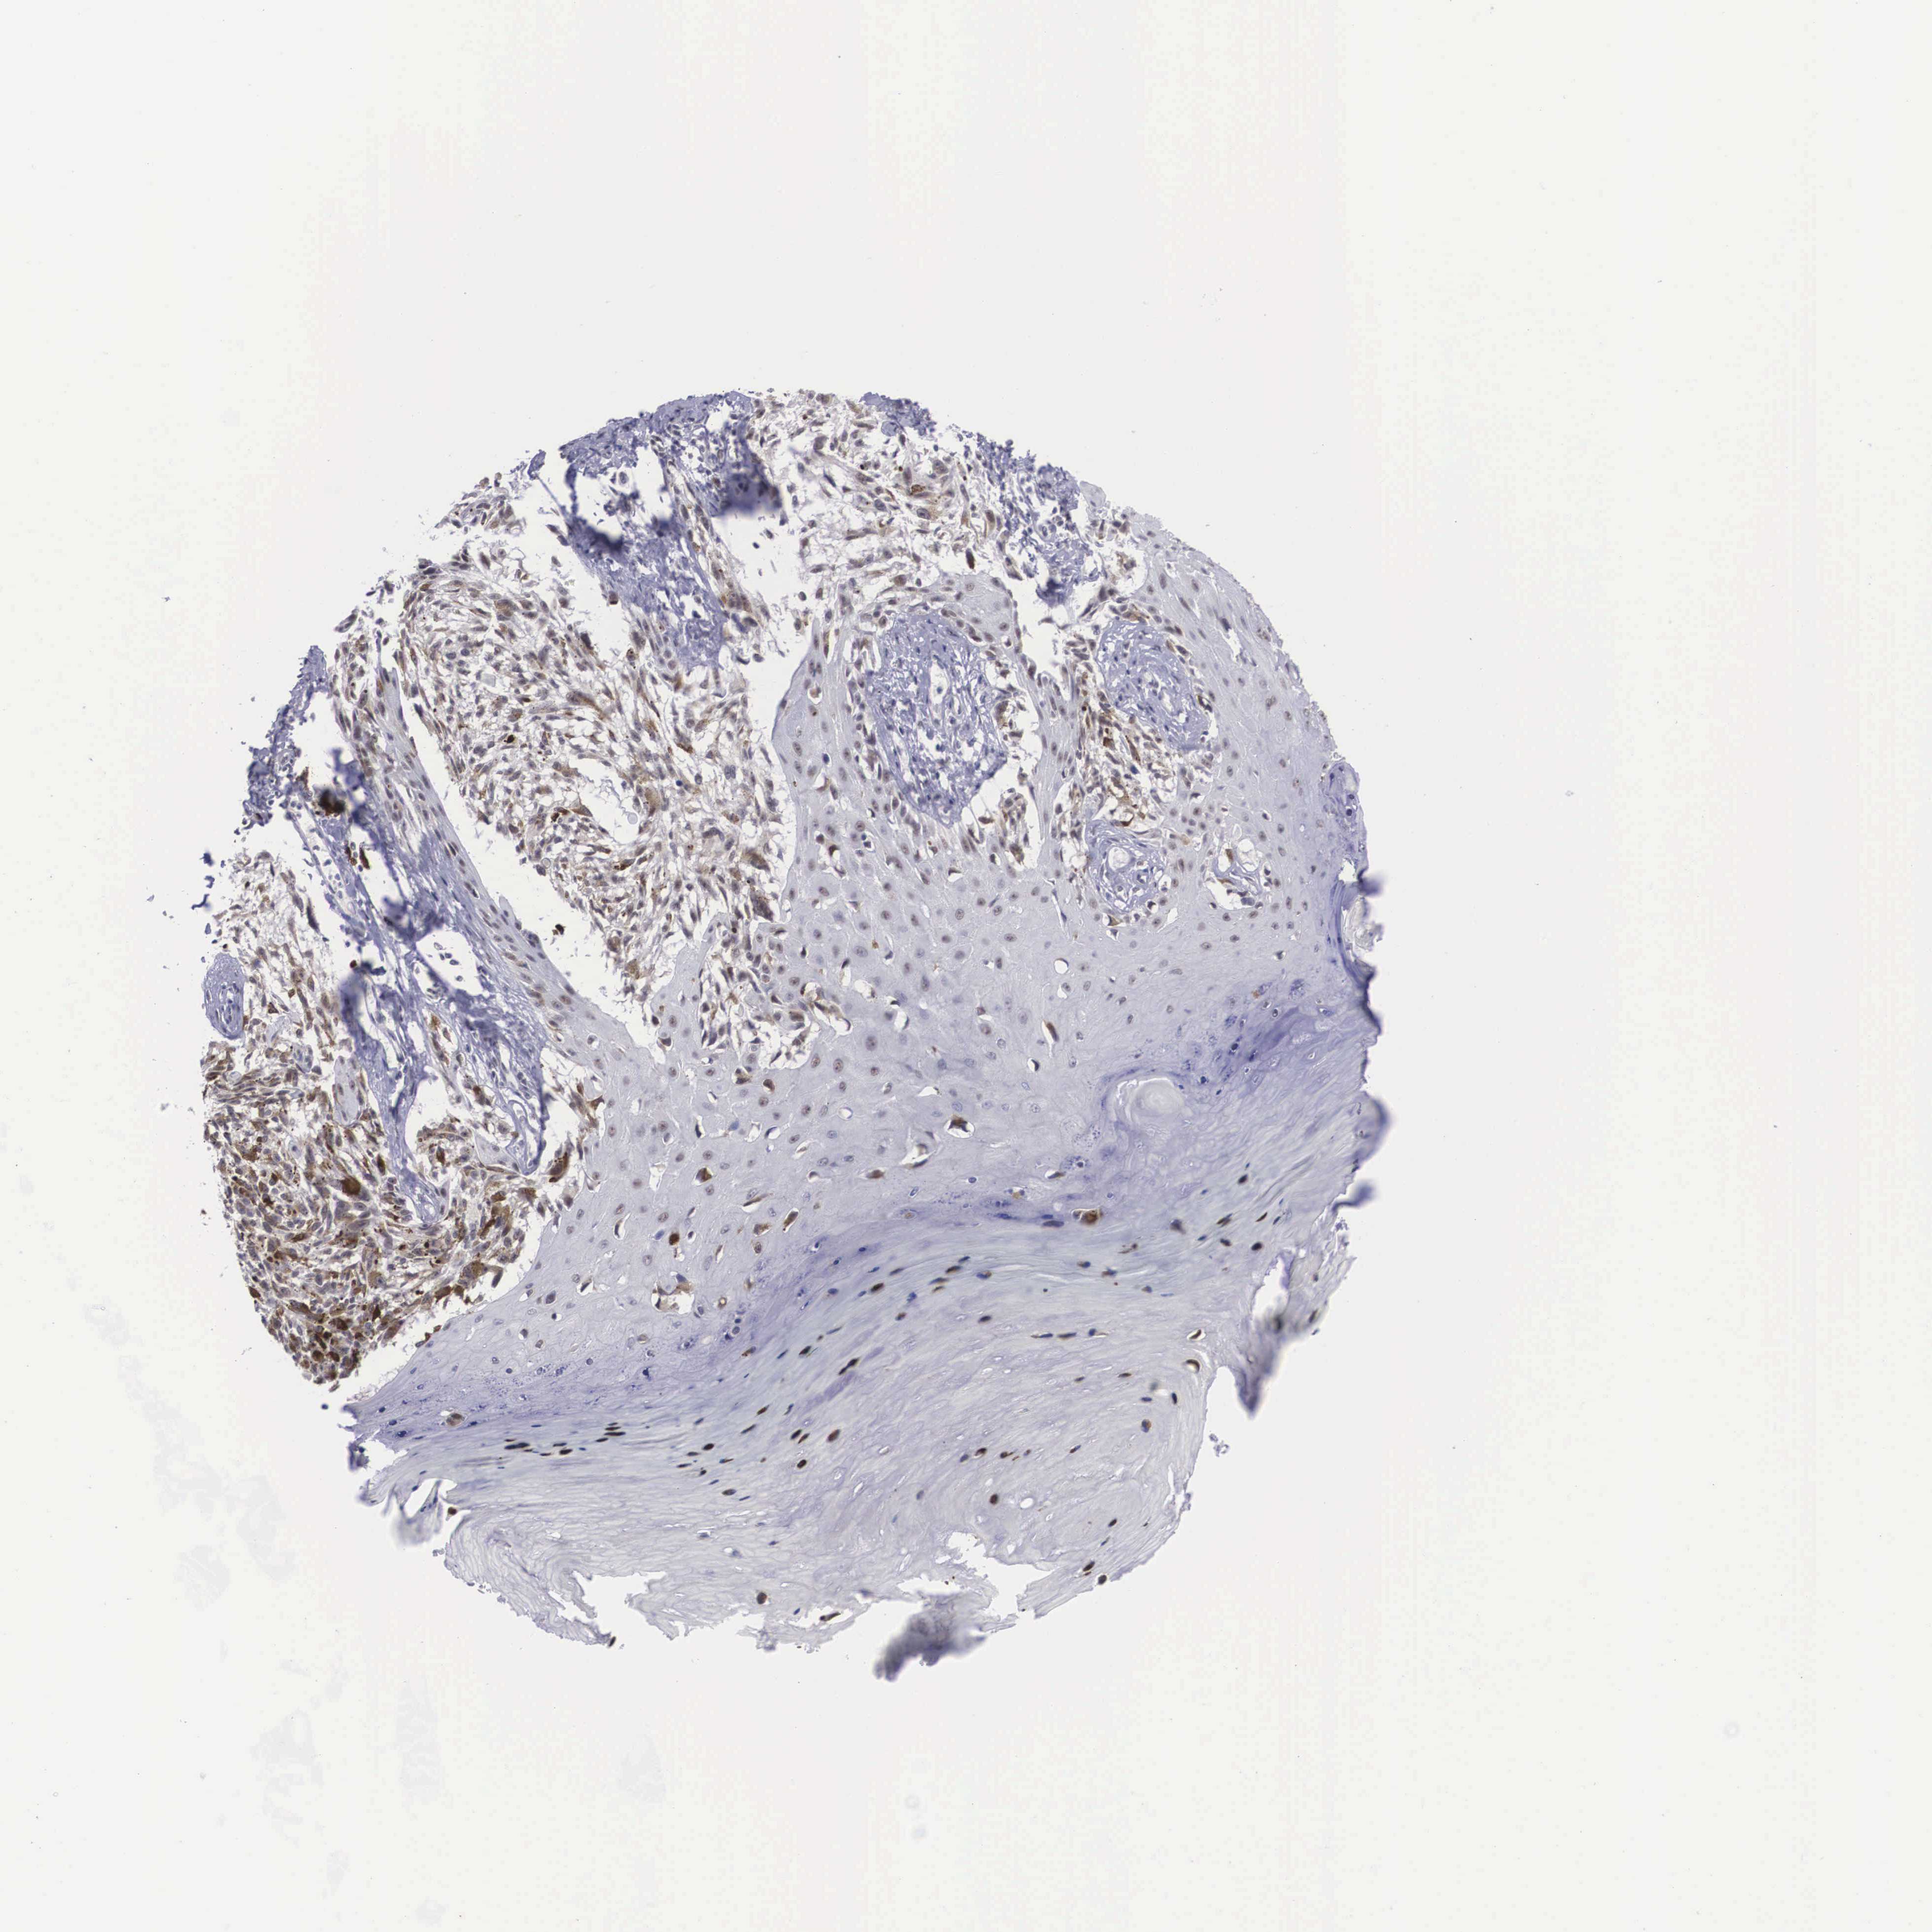

MELANOMA - Protein expressioni

A mouse-over function shows sample information and annotation data. Click on an image to view it in a full screen mode. Samples can be filtered based on level of antibody staining by selecting one or several of the following categories: high, medium, low and not detected. The assay and annotation is described here.

Note that samples used for immunohistochemistry by the Human Protein Atlas do not correspond to samples in the TCGA dataset.

Antibody stainingi

Antibody staining in the annotated cell types in the current human tissue is reported as not detected, low, medium, or high, based on conventional immunohistochemistry profiling in selected tissues. This score is based on the combination of the staining intensity and fraction of stained cells.

Each image is clickable and will lead to virtual microscopy that enables deeper exploration of all samples and also displays staining intensity scores, fraction scores and subcellular localization as well as patient and tissue information for each sample.

Antibody HPA000566

Staining

High

Medium

Low

Not detected

Intensity

Strong

Moderate

Weak

Negative

Quantity

>75%

75%-25%

<25%

None

Location

Nuclear

Cytoplasmic/membranous

Cytoplasmic/membranous,nuclear

Malignant melanoma, NOS

Malignant melanoma, Metastatic site